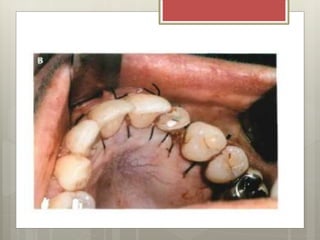

SECUENCIA DE LA SUTURA

SECUANCIA DE LA SUTURA